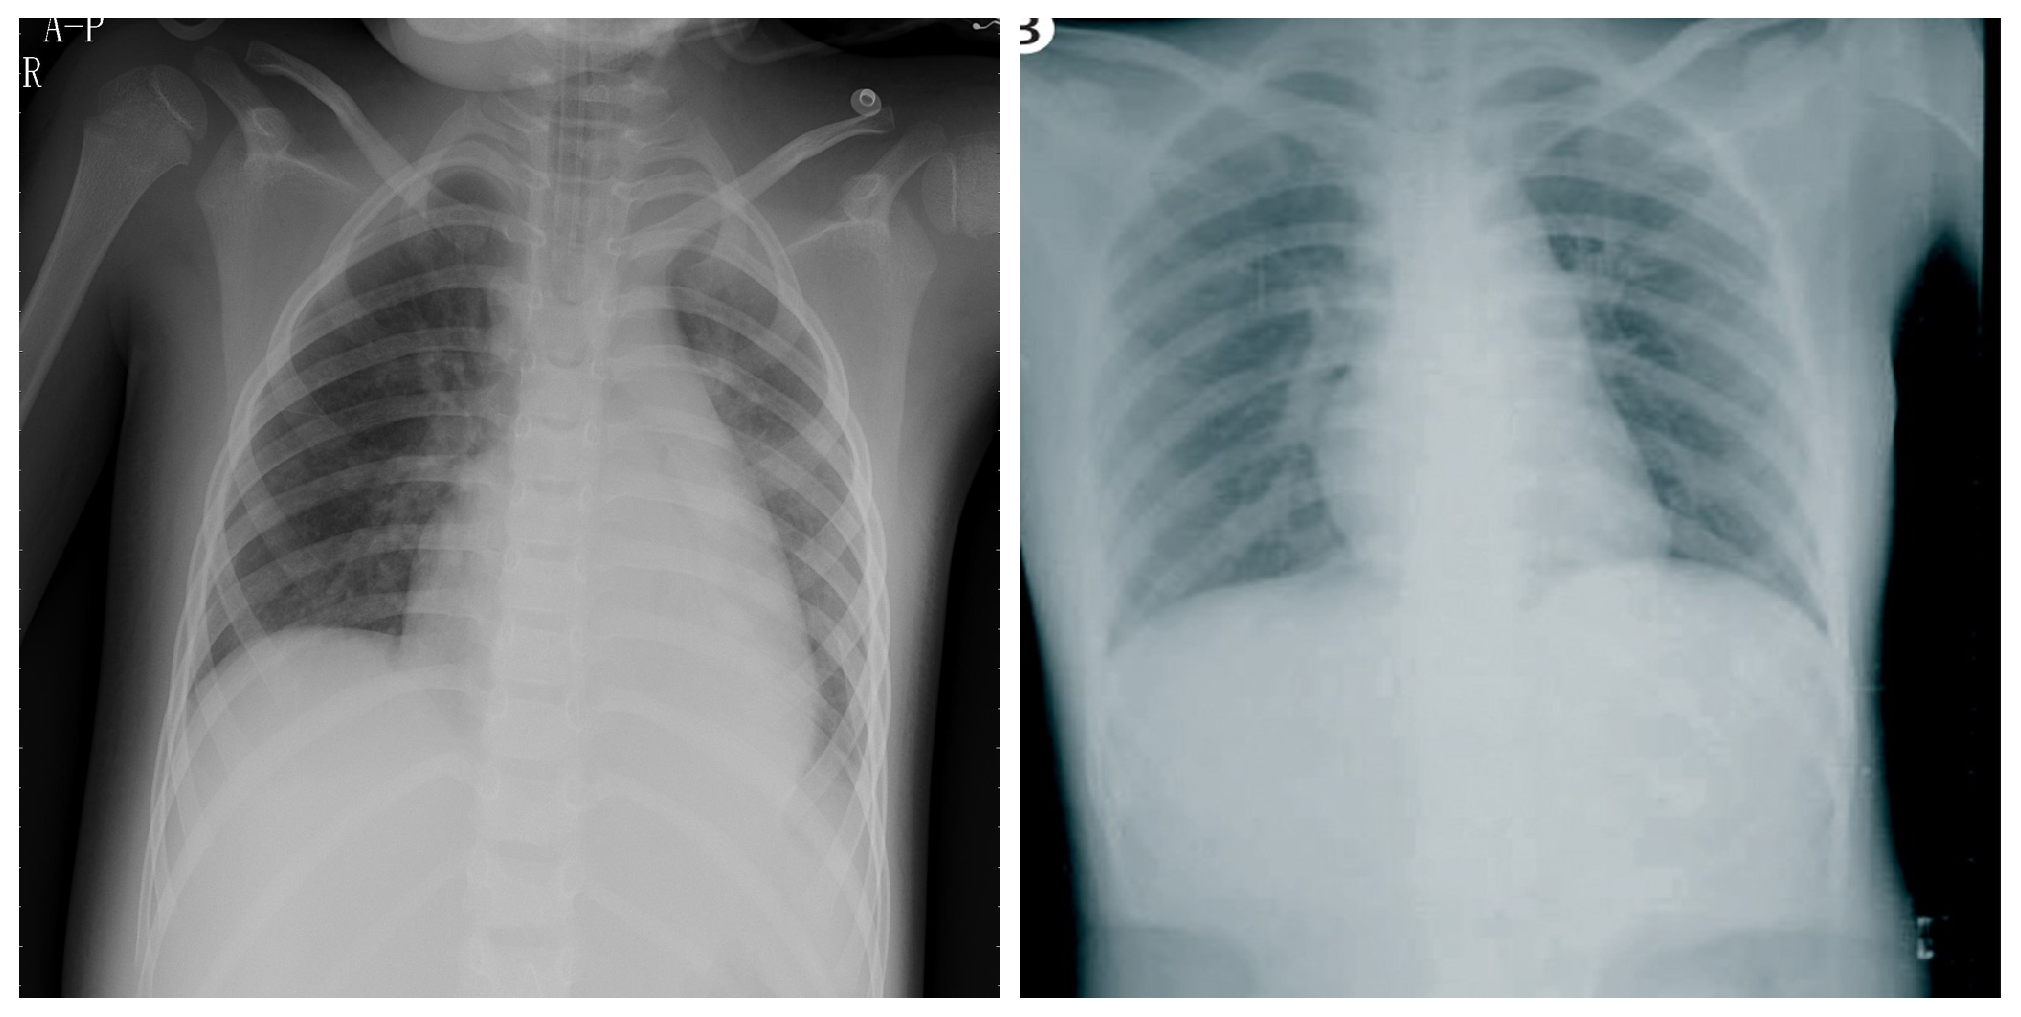

3.1. COVID-19 Image Data Collection (CIDC)

3.2. COVID-19 Radiography

3.3. BIMCV COVID19+

3.4. RSNA

3.5. Chest X-ray Images Pneumonia (CXRIP)